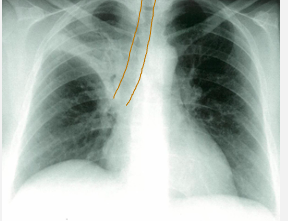

What does this CXR indicate? - Pneumoperitoneum - Pneumothorax - Pulmonary oedema - Consolidation - Pleural effusion

What does this CXR indicate? - Pneumoperitoneum - Pneumothorax - Pulmonary oedema - **Consolidation** - Pleural effusion